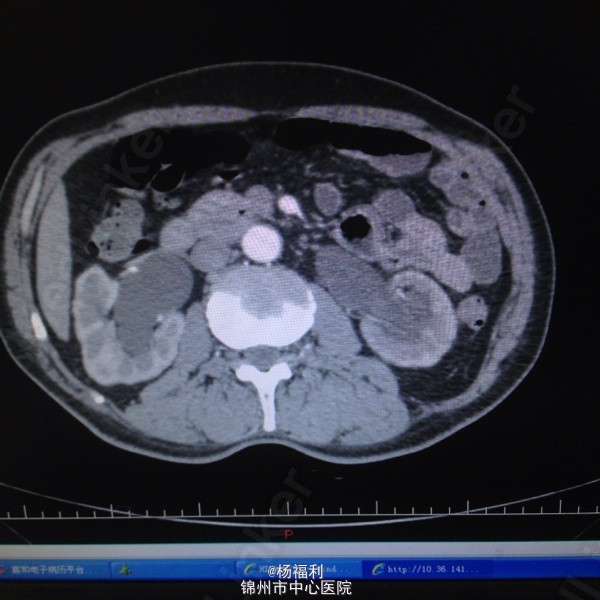

71岁男患,5年前即开始出现尿频,尿急。夜尿3-4次。排尿困难。无发热、无腰痛,无肉眼血尿。一直未与治疗。症状进行性加重。半月前患者排尿困难症状严重,尿滴沥。伴右腰部疼痛来我院就诊。

双肾区无叩击痛。双输尿管走形区无压痛,耻骨上区压痛。叩诊浊音。前列腺指诊前列腺增大,中央沟消失,质韧。未触及硬结及肿物。 彩超;双肾积水,前列腺增大突入膀胱,膀胱肌小梁形成。 ctu:前列腺增生。双侧肾盂及输尿管扩张,左肾多发小囊肿。 膀胱镜:前列腺增大突入膀胱,膀胱内多发小房小梁。 总psa:4.6ng/ml,比值:0.18。 肌酐:175umol/l。 尿常规:白细胞2+。

1、尿潴留2、前列腺增生症3、双肾及输尿管积水4、泌尿系感染。 给予患者留置尿管后择期行经尿道前列腺等离子电切术。 患者家里条件不太好,要求给予快速手术。未等肌酐及积水好转后即给予手术。

术后病理良性。拔除尿管后排尿良好。 建议患者术后半月复查泌尿系彩超查看积水情况。 此类患者必须等肌酐及积水完全恢复后手术吗?留置尿管多长时间积水可以消失? 此种积水术后可以完全消失吗 ?术后排尿无阻力情况下多久可以完全消失?欢迎大家讨论。让患者多久复查彩超好些?